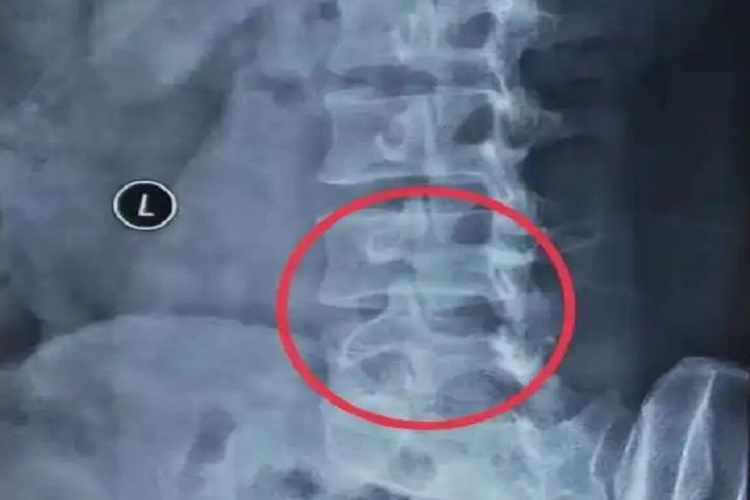

腰椎狗头征指X线腰椎45°斜位摄片上可见腰椎横突轮廓似狗头状,是椎弓崩裂的征象,属于腰椎滑脱。椎弓崩裂滑脱发病年龄在4岁以后,以12-16岁发病。起始症状较轻,以后可出现持续腰痛或合并腿痛,卧床休息时缓解、活动加重。下肢痛可放射至小腿及足背或足外侧,严重的患者可出现双侧下肢和大、小便功能障碍。